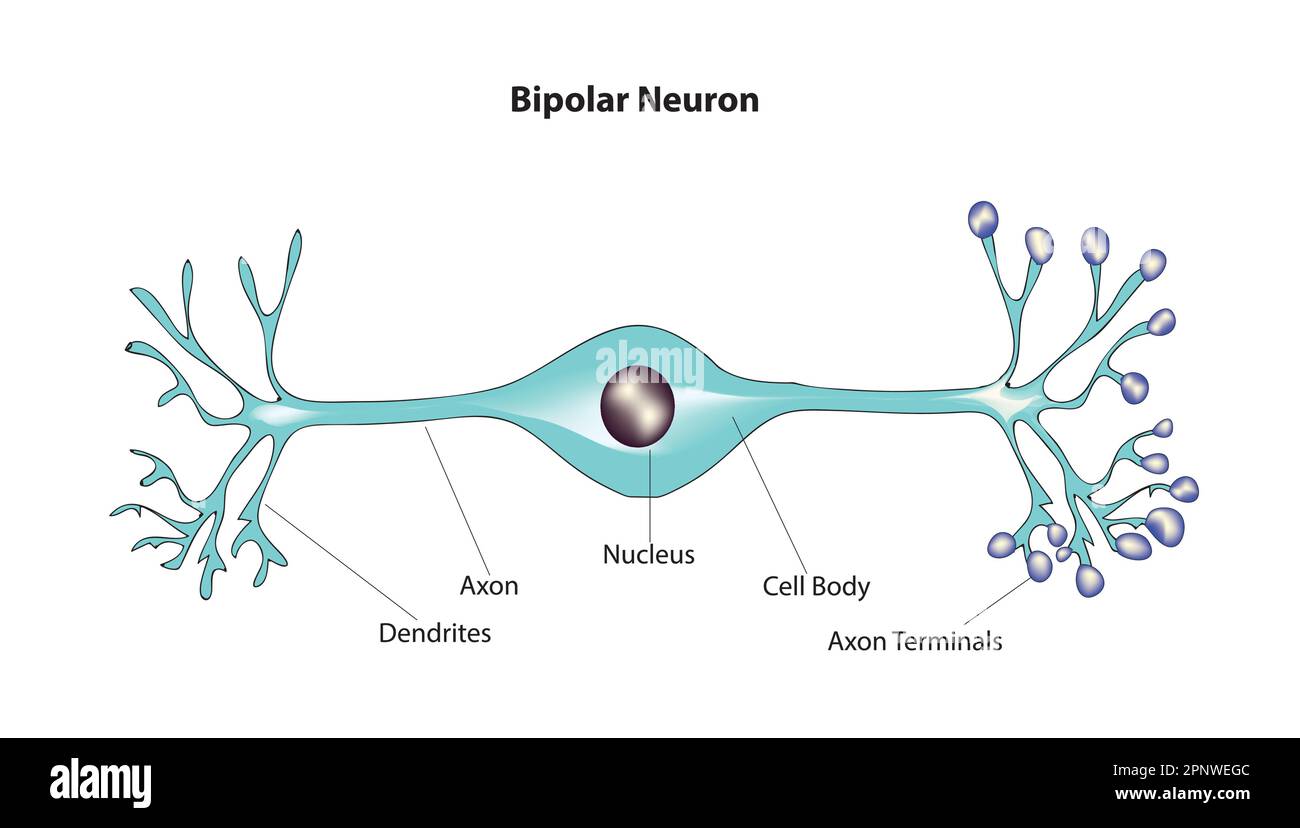

RF2J7343T–Tipi di neuroni: Cellule piramidali della corteccia cerebrale, cellule Purkinje della corteccia cerebrale, cellule olfattive dell'epitelio olfattivo

RF2WNK1GK–La struttura di un neurone malato e sano. Neurone danneggiato. Malattia di Alzheimer. Malattia cerebrale demenza, disturbi della memoria. Un neurone nell'Alzheimer